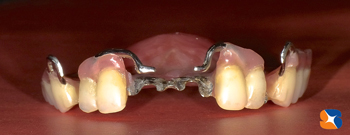

開業時から、入れ歯の強度を向上させるためにデザイン加工した補強金属を多様してきました。

自費の入れ歯で用いるバネ金具を採算度返しで惜しみなく保険の入れ歯に使用してきました。

20年経った今もそれは続けています。

「目立たない、取り外しが簡単、安定感抜群」そんなごく当たり前(当院では)の入れ歯を10回にわたって紹介していきます。